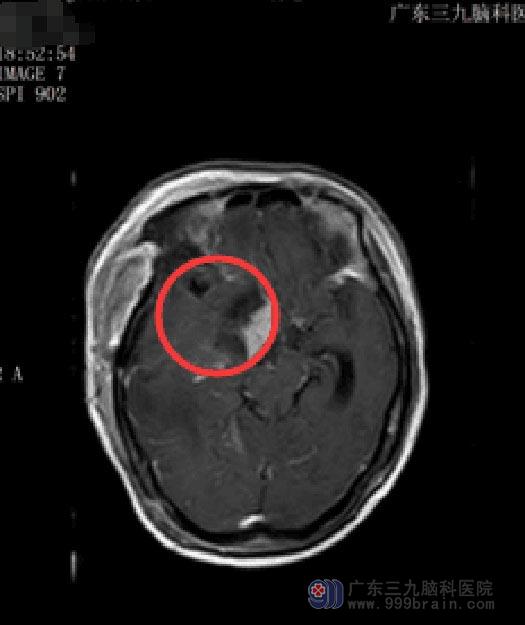

在确认小娟没有绝对手术禁忌症后,鲁明副院长主刀行“右侧前中颅窝脑膜瘤切除术”,术中暴露中颅窝底,见灰白色肿瘤,质韧,有完整包膜,血供较丰富,分块切除肿瘤,术中颈内动脉、大脑中动脉、大脑前动脉、视神经、动眼神经均保护完整。术后小娟肢体乏力症状明显好转。术后病理提示:脑膜皮细胞型脑膜瘤,WHO I级。